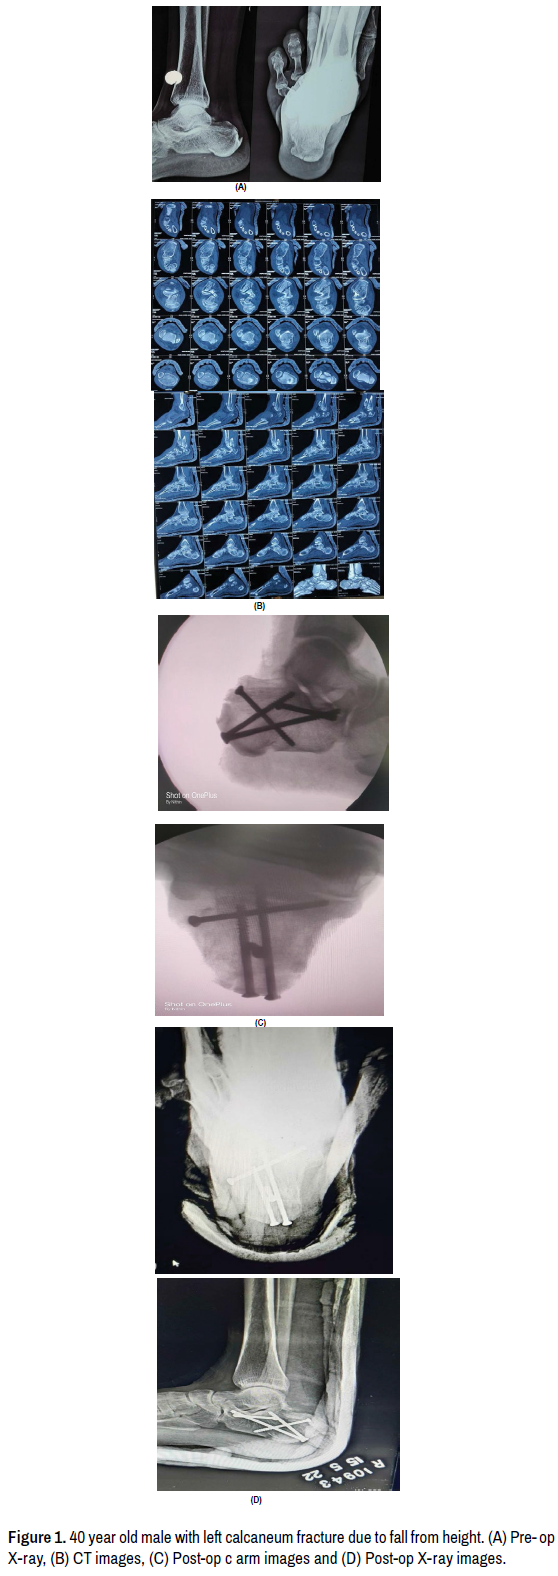

Here are few of the examples of cases which were managed accordingly (Figures 1 and 2).

Figure 1. 40 year old male with left calcaneum fracture due to fall from height. (A) Pre- op X-ray, (B) CT images, (C) Post-op c arm images and (D) Post-op X-ray images.